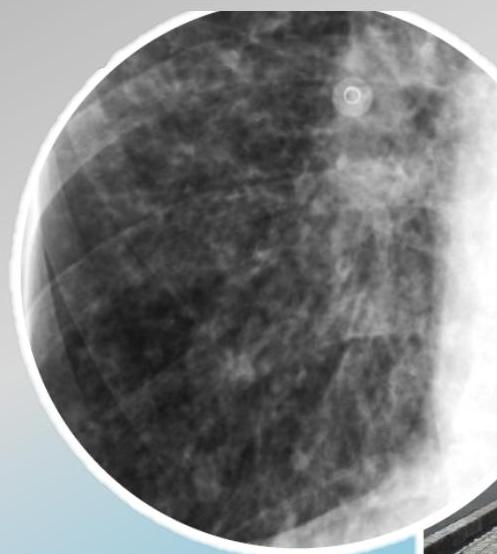

Radiographic Findings (Signs)

Bronchial wall thickening and widening with parallel configuration. Tram track sign.